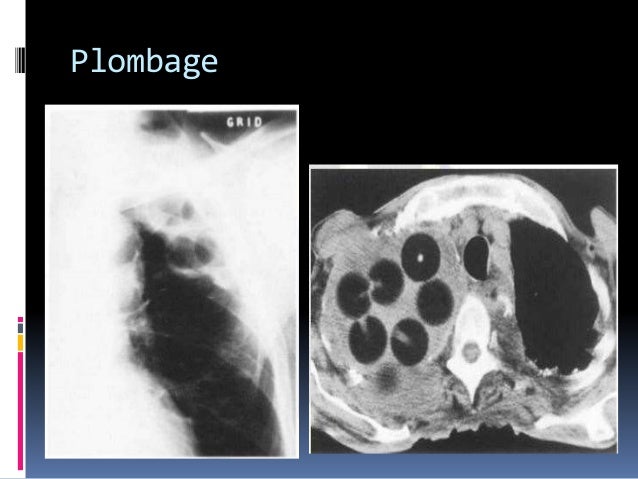

Lucite Ball Plombage Nejm

Learningradiology Thoracoplasty Ping Pong Ball Plumbage Older